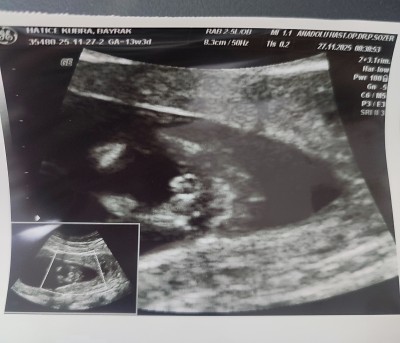

11 haftalık ve 13+5 haftalık ultrason görüntülerimiz doktor cinsiyette emin olamadi önce erkek sonra kız dedi ama sizin tahminleriniz neler?

Gebelik haftası 13+5

Bacak arasında uç cızgı var gıbı canm kıza benzettim bende

Kız hissettim

Kız sanki☺️